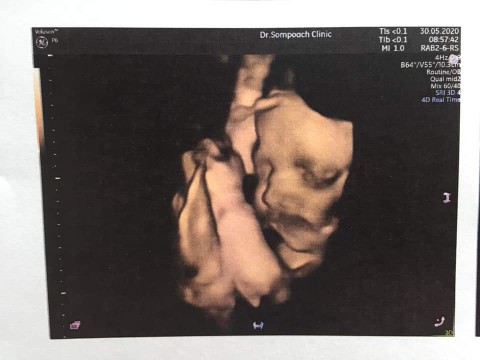

ซาวด์ตอน8เดือนจ้า